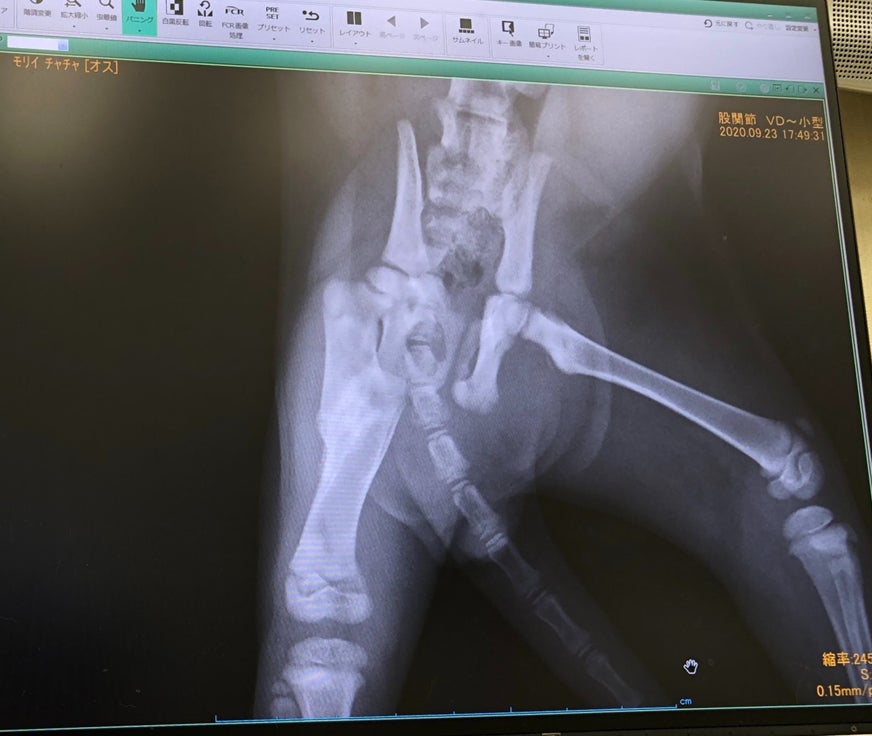

先日病院を受診してレントゲンを撮ってもらいましたが、骨折はちゃんと引っ付いたようで一安心です。